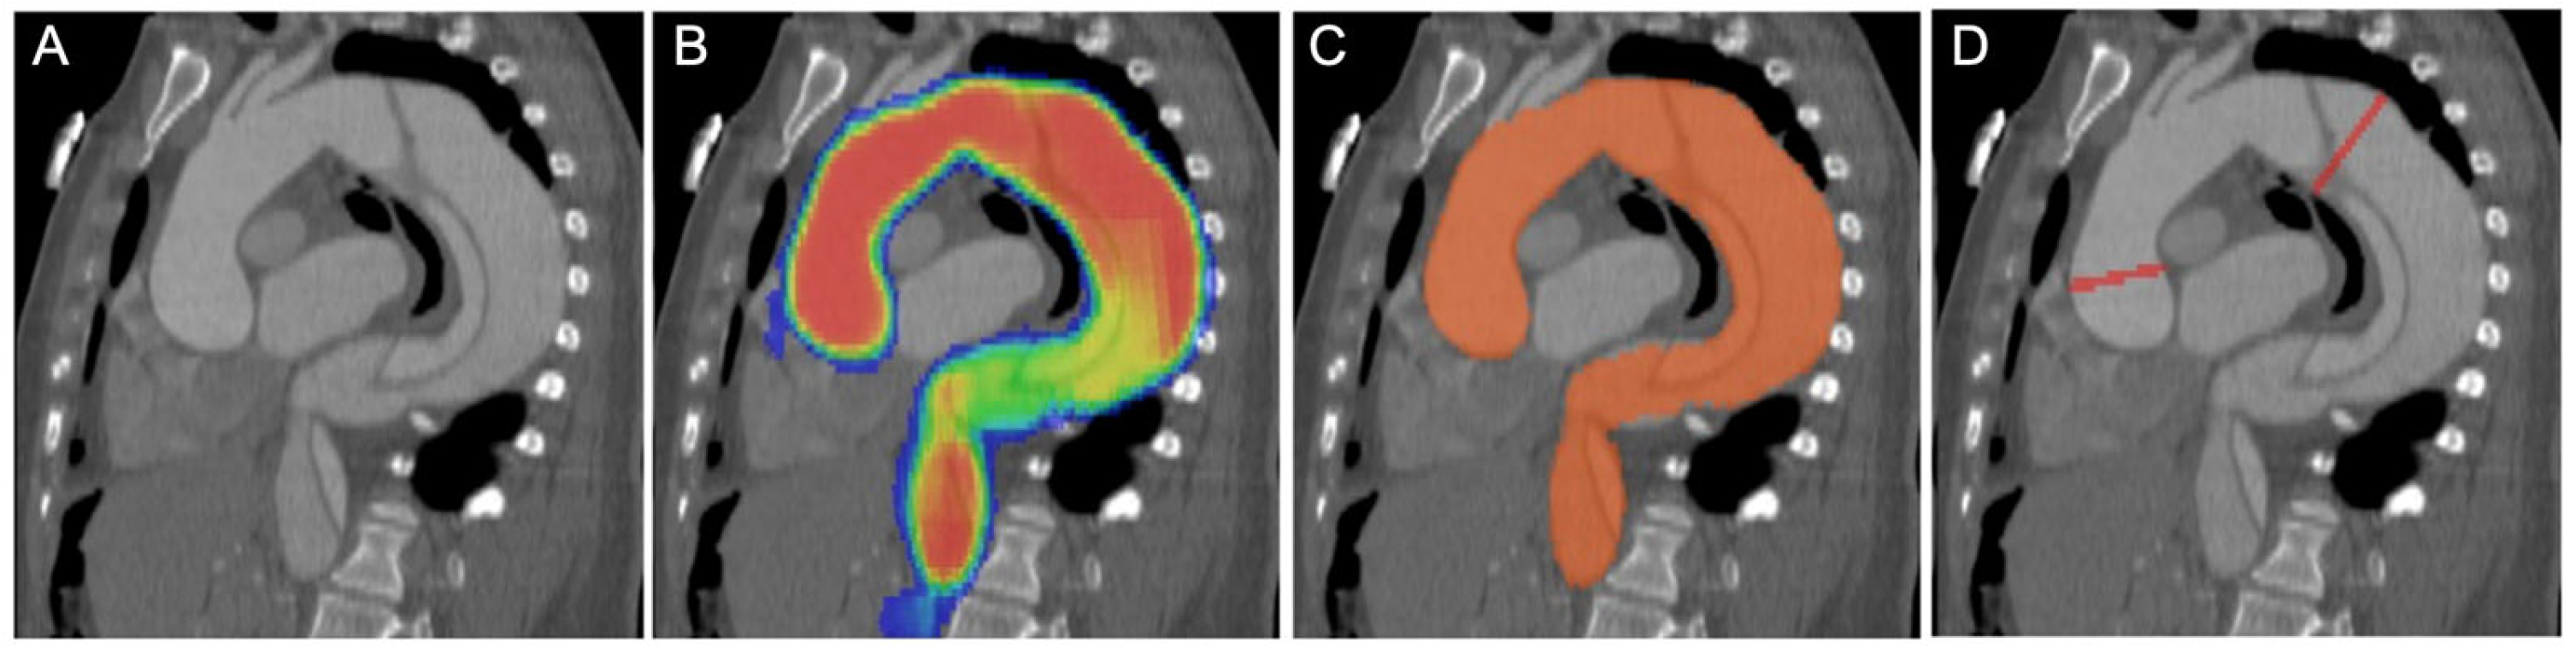

2.3. Convolutional Neural Network Model and Measurements